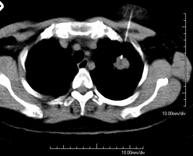

- TC Cuello Prueba radiológica que consiste en obtener imágenes del cuello de alta definición anatómica mediante el empleo de un equipo de TC (Tomografía Computarizada). Indicaciones: estudio de tiroides, control de tumores tratados, estudio de ganglios, infecciones y abscesos. Prueba radiológica que consiste en obtener imágenes del cuello de alta definición anatómica mediante el empleo de un equipo de TC (Tomografía Computarizada). Indicaciones: estudio de tiroides, control de tumores tratados, estudio de ganglios, infecciones y abscesos.

- Tórax- TC Tórax Prueba diagnóstica que consiste en obtener imágenes del tórax de alta definición anatómica (pulmones, corazón, mediastino, grandes vasos, caja torácica, etc.) mediante el empleo de un equipo de TC (Tomografía Computarizada). Dichas imágenes se estudian posteriormente en una estación de trabajo que permite reconstrucciones bidimendionales en diferentes planos del espacio y también reconstrucciones 3D (volumétricas). Algunos estudios requieren el empleo de contraste yodado para mejorar la definición de las imágenes. Prueba diagnóstica que consiste en obtener imágenes del tórax de alta definición anatómica (pulmones, corazón, mediastino, grandes vasos, caja torácica, etc.) mediante el empleo de un equipo de TC (Tomografía Computarizada). Dichas imágenes se estudian posteriormente en una estación de trabajo que permite reconstrucciones bidimendionales en diferentes planos del espacio y también reconstrucciones 3D (volumétricas). Algunos estudios requieren el empleo de contraste yodado para mejorar la definición de las imágenes.

- TC de coll Prova radiològica que consisteix en obtenir imatges del coll d'alta definició anatòmica, mitjançant l'ús d'un equip de TC (Tomografia Computeritzada). Prova radiològica que consisteix en obtenir imatges del coll d'alta definició anatòmica, mitjançant l'ús d'un equip de TC (Tomografia Computeritzada).

- TC Tòrax Prova diagnòstica que consisteix en obtenir imatges del tòrax d'alta definició anatòmica (pulmons, cor, mediastí, grans vasos, caixa toràcica, etc.) mitjançant l'ús d'un equip de TC (Tomografia Computeritzada). Aquestes imatges s'estudien posteriorment en una estació de treball que permet reconstruccions bidimensionals en diferents plans de l'espai i també reconstruccions tridimensionals (3D: volumètriques). Alguns estudis requereixen l'ús de contrast iodat per millorar la definició de les imatges. Prova diagnòstica que consisteix en obtenir imatges del tòrax d'alta definició anatòmica (pulmons, cor, mediastí, grans vasos, caixa toràcica, etc.) mitjançant l'ús d'un equip de TC (Tomografia Computeritzada). Aquestes imatges s'estudien posteriorment en una estació de treball que permet reconstruccions bidimensionals en diferents plans de l'espai i també reconstruccions tridimensionals (3D: volumètriques). Alguns estudis requereixen l'ús de contrast iodat per millorar la definició de les imatges.